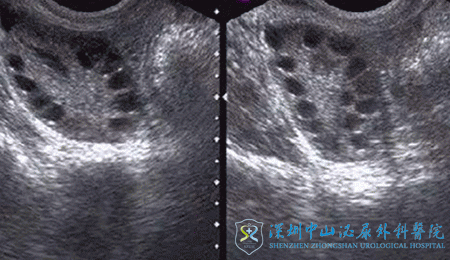

2018年8月,黄女士夫妇经朋友的介绍来到深圳中山妇产医院咨询王雪金医生,王雪金医生详细地了解了黄女士的生育史和既往病史,亲自做了经阴道彩超,发现黄女士的子宫内膜较厚且回声不均匀,考虑黄女士有多囊卵巢综合征的病史,存在子宫内膜病变的高危因素,遂建议黄女士先行宫腔镜检查排除子宫内膜病变。

2018年9月,黄女士在宫腔镜检查后发现存在多发性子宫内膜息肉,遂行子宫内膜息肉切除术,术后调养了一段时间,黄女士再次回到医院咨询王雪金医生。因子宫内膜息肉有复发倾向,故王雪金医生建议黄女士尽快进入促排周期。并于2018年11月开始促排,最终获卵10枚,移植2个优质卵裂胚胎,冷冻1个囊胚。